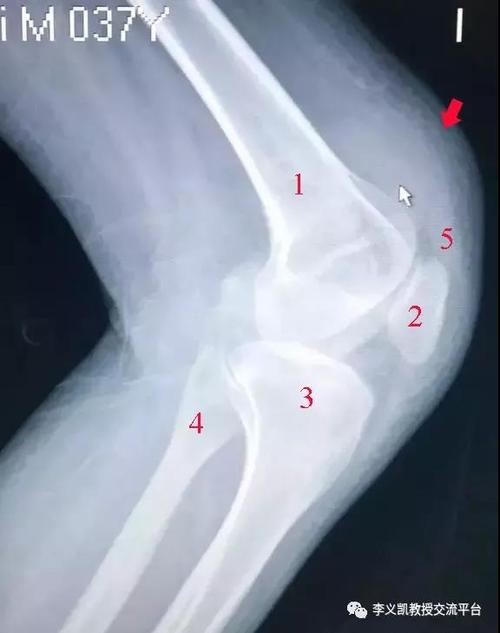

髌上囊积液图片,髌上囊积液

髌上囊积液x线图片

髌上囊积液x线